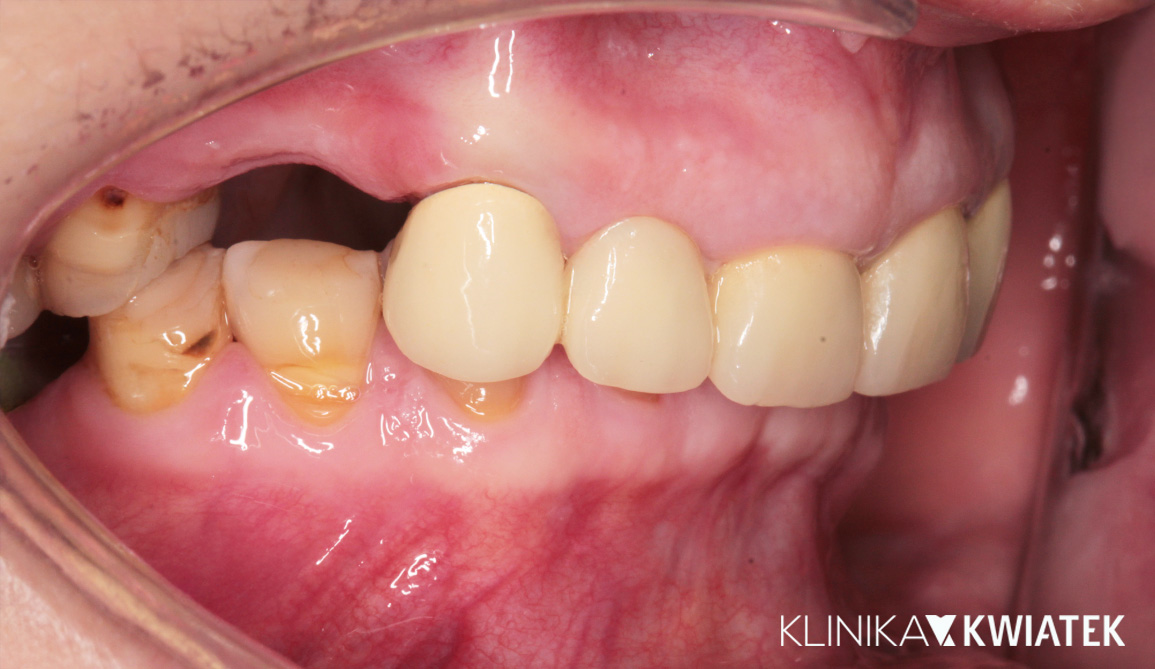

Pacjent zgłosił się z przewlekłym stanem zapalnym i bólem zęba 26, którego nie dało się już uratować leczeniem zachowawczym. Po dokładnej diagnostyce wykonano atraumatyczną ekstrakcję z zastosowaniem materiału PRF i biomateriału kościozastępczego, połączoną z podniesieniem dna zatoki szczękowej. Następnie, po okresie gojenia, wszczepiono implant MIS C1. Zwieńczeniem leczenia była precyzyjnie dopasowana korona ceramiczna, przywracająca pełną funkcję i estetykę uśmiechu.

Warto podkreślić, że decyzja o ekstrakcji nie jest dziś końcem leczenia, lecz początkiem nowoczesnej odbudowy. W naszej klinice wykorzystujemy zaawansowane techniki implantologiczne i regeneracyjne, które na co dzień pozwalają skutecznie zastąpić utracony ząb – trwale, bez bólu i z naturalnym efektem estetycznym.